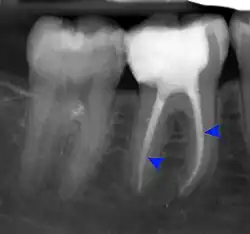

Apical periodontitis

Apical abscess associated with roots of a lower molar.

Apical periodontitis is acute or chronic inflammation around the apex of a tooth caused by an immune response to bacteria within an infected pulp.[20] It does not occur because of pulp necrosis, meaning that a tooth that tests as if it's alive (vital) may cause apical periodontitis, and a pulp which has become non-vital due to a sterile, non-infectious processes (such as trauma) may not cause any apical periodontitis.[10]: 225  Bacterial cytotoxins reach the region around the roots of the tooth via the apical foramina and lateral canals, causing vasodilation, sensitization of nerves, osteolysis (bone resorption) and potentially abscess or cyst formation.[10]: 228

The periodontal ligament becomes inflamed and there may be pain when biting or tapping on the tooth. On an X-ray, bone resorption appears as a radiolucent area around the end of the root, although this does not manifest immediately.[10]: 228  Acute apical periodontitis is characterized by well-localized, spontaneous, persistent, moderate to severe pain.[6]: 125–135  The alveolar process may be tender to palpation over the roots. The tooth may be raised in the socket and feel more prominent than the adjacent teeth.[6]: 125–135